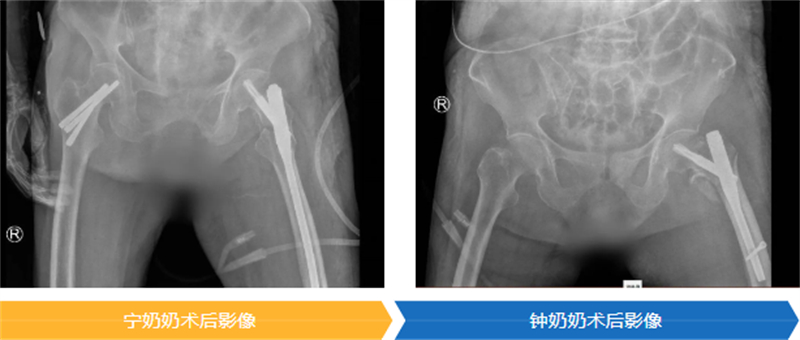

手術是讓老人重獲生機的關鍵一步,但同時也是對百歲高齡軀體的嚴峻挑戰。為了以最小的創傷換取最大的生存機會,醫療團隊為兩位老人精心選擇了“股骨近端防旋髓內釘(PFNA)”這一微創固定方案。

舒文主任醫師對此做了一個生動的比喻:“這個手術就像是處理一個內部斷裂的承重墻。不需要‘大拆大建’,只需通過一個很小的切口,在骨頭內部植入一個堅固的‘內置支架’,為骨折部位提供穩定支撐,如同架起一根‘鋼筋’,讓老人能夠盡早活動,從而避免臥床帶來的各種致命風險?!?/p>

時間就是生命。在醫院為高齡患者開通的綠色通道保障下,兩位老人均在入院24小時內接受了這關鍵性手術,并順利完成。隨后,在重癥監護室(ICU)團隊的晝夜精心守護下,兩位百歲老人平穩渡過了術后最危險的階段,為后續的康復贏得了寶貴的時機。

在大家溫暖的鼓勵和專業的幫助下,寧奶奶在手術后第三天,就穩穩地站起來了;鐘奶奶也在第五天,堅強地扶著助行器邁開了步子。能早點下床,就意味著能把肺炎、血栓這些“臥床病”遠遠推開,恢復得更順利,也能早一點回家。